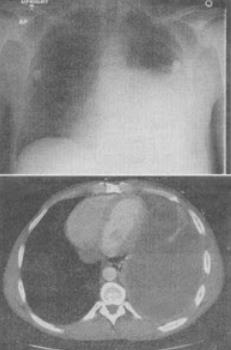

- 单项选择题 患者,男,48岁,呼吸困难、胸痛,结合CT图像,最可能的诊断是()。

A、支气管胸膜瘘

B、肺结核

C、吸入性肺炎

D、肺囊虫病

E、肺脓肿

- A